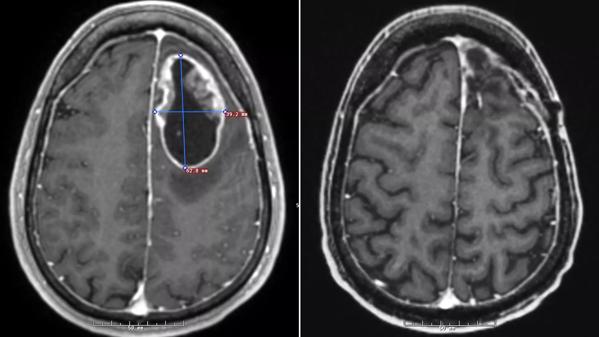

“While we are still in the relatively early phases of testing this vaccine, we are seeing some very promising results which give us a lot of hope for this patient population,” explained Dr. Ahluwalia. “In Jeff’s case, he has gone almost 18 months from his diagnosis, and – on his recent MRI scans — we do not see any evidence of cancer growing going back in his brain.”

An MRI of Jeff’s tumor before surgery (left) and recently, after treatment (right), with no evidence of tumor growth. (Courtesy: Cleveland Clinic)

SurVaxM stimulates the immune system to kill tumor cells that contain survivin, a protein that helps cancer cells resist conventional treatments. Preliminary results of the first 55 patients in the SurVaxM trial reveal a 12-month overall survival rate of 90.9 percent from diagnosis and 70.8 percent from first immunization, a vast improvement over traditional treatment alone. Jeff and other patients experienced few if any side effects. Researchers now plan to conduct a randomized, prospective trial of SurVaxM for GBM patients.